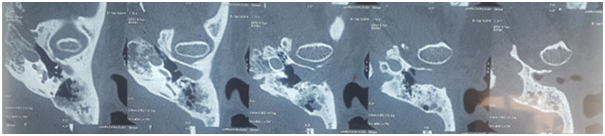

A 47-year-old Moroccan female with a past medical history of NPC [2009] treated with chemo radiation therapy, presented to the ENT department of University hospital of Casablanca for repeated left ear purulent discharge over the past 6 months and a progressive hearing loss. Otoscopic examination revealed a tissue mass filling the left EAC. Temporal bone CT scan revealed a soft tissue density filling the EAC [polyp], enhancing after injection of contrast product. The tissue process encroaches upon the tympanic cavity and comes into contact with the handle of the malleus with neither detectable ossicular lysis nor EAC walls erosion (Figure 1). The biopsy of the mass was consistent with squamous cell carcinoma of the left EAC. The patient underwent lateral temporal bone resection with homolateral superficial parotidectomy and neck dissection. Anatomopathological examination of the specimen substantiated a well differentiated keratinizing and infiltrating squamous cell carcinoma of the left EAC. Resection margins were affected but the parotid specimens were healthy. The surgical management was completed by adjuvant external radiotherapy. Immediately in postoperative check-up, the patient presented left peripheral facial palsy (House III) (Figure 2). One year follow-up, the patient lives with no signs of recurrence.